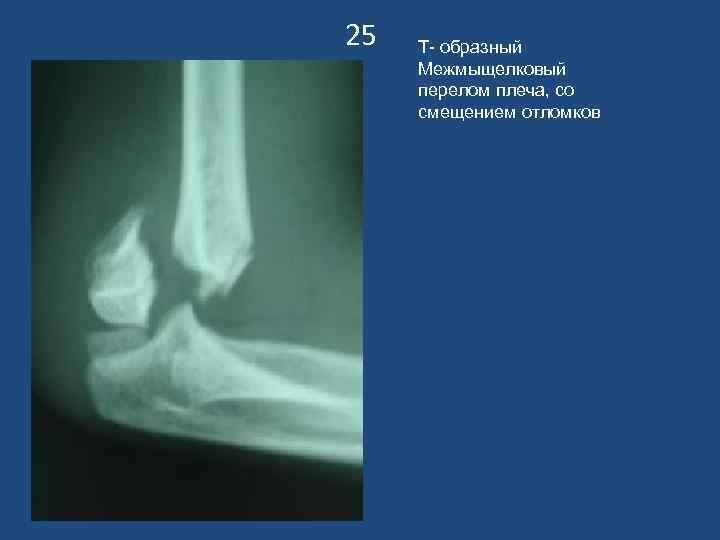

25 Т- образный Межмыщелковый перелом плеча, со смещением отломков